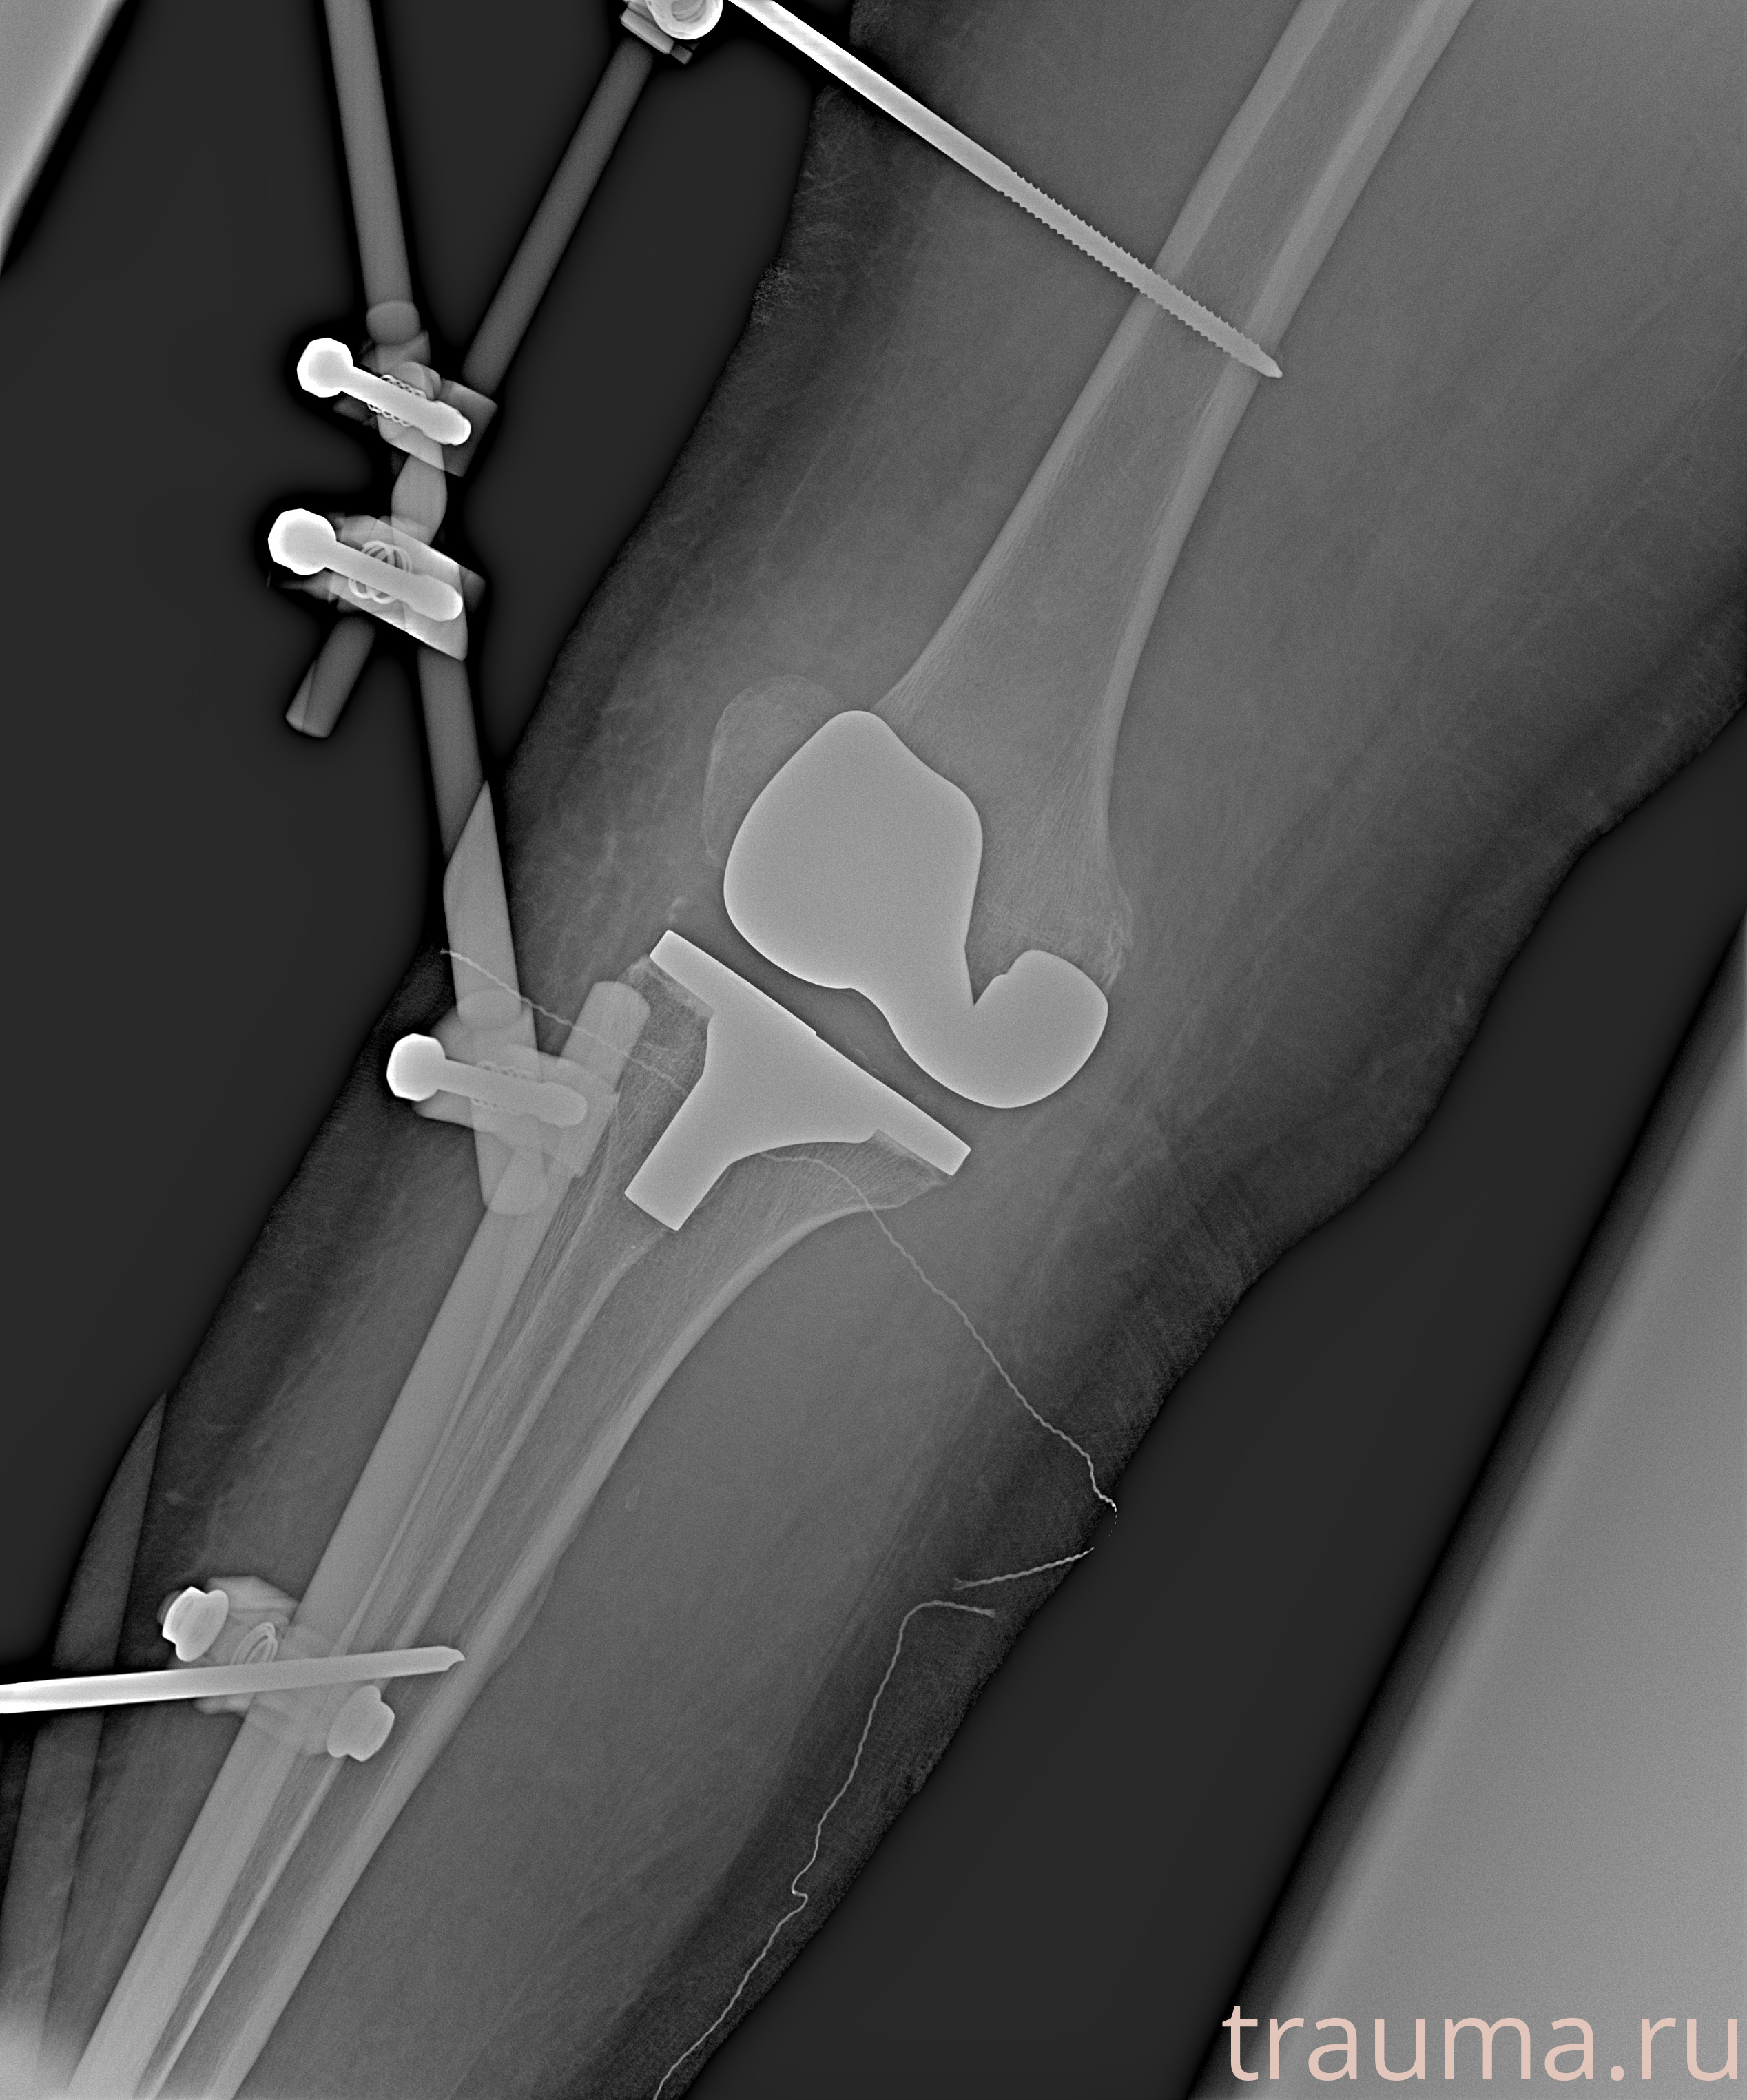

Рентген на дому: по вашему адресу приезжает врач-рентгенолог, травматолог-ортопед с мобильным рентгеновским аппаратом, проводит диагностику травмы или заболевания, делает необходимые рентгенограммы, дает рекомендации по дальнейшему лечению. Получить качественные снимки в домашних условиях возможно благодаря уникальной методике, разработанной МосРентген Центром для института  Склифосовского